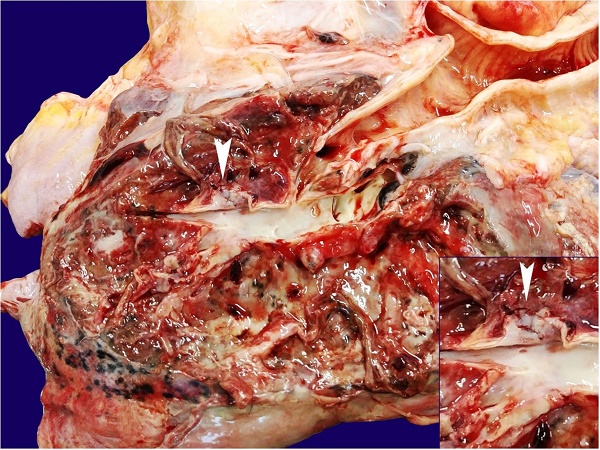

External examination revealed a cachectic corpse with cutaneous and mucosal pallor and thoracotomy in the posterolateral region of the right thorax. Internal examination revealed mucosanguinolent fluid in the trachea and bronchi. The right lung weighed 355 g (reference range = 360-570g1) and contained an abscess in the lower lobe, measuring 12.5 × 8.5 cm. The right lower lobar pulmonary artery also harbored a ruptured aneurysm (Figure 4), which was later confirmed by microscopy with the aid of histochemical staining (Figure 5).

Microscopic examination of the lung revealed extensive liquefactive necrosis, associated with dense purulent inflammation (Figures 66D) and infiltration of filamentous fungi and spores (Figures 77B). Sparse foci of bronchopneumonia were detected on the remaining lung parenchyma. Other organs showed generalized visceral pallor, mild hydrocephalus ex-vacuo, and mild cerebral atrophy, with no additional pathology in the remaining organs. Death was attributed to massive pulmonary hemorrhage due to the rupture of the right lower lobar artery aneurysm, resulting from a chronic lung abscess formed in the right lower lobe.